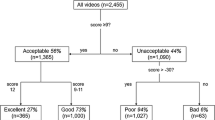

Microcirculatory disorders are crucial in pathophysiology of organ dysfunction in critical illness. Evaluation of sublingual microcirculation is not routinely conducted in daily practice due to time-consuming analysis and susceptibility to artifacts. We investigated the suitability of optical coherence tomography angiography (OCTA) for contactless evaluation of sublingual microcirculation. Sublingual microcirculation was imaged in 10 healthy volunteers, using an OCTA device and an incident dark field (IDF) illumination microscopy (current gold standard). OCTA images were analyzed with regard to flow density and perfused vessel density (PVDbyOCTA). IDF videos were analyzed following current recommendations. Flow density was automatically extracted from OCTA images (whole en face 48.9% [43.2; 54.5]; central ring 52.6% [43.6; 60.6]). PVDbyOCTA did not differ from the PVD calculated from IDF videos (PVDbyOCTA 18.6 mm/mm² [18.0; 21.7]) vs. PVDbyIDF 21.0 mm/mm² [17.5; 22.9]; p = 0.430). Analysis according to Bland-Altman revealed a mean bias of 0.95 mm/mm² (95% Confidence interval −1.34 to 3.25) between PVDbyOCTA and PVDbyIDF with limits of agreement of −5.34 to 7.24 mm/mm². This study is the first to demonstrate the suitability of OCTA for evaluating sublingual microcirculation. Comparison of the perfused vessel density between methods showed a plausible level of agreement.

The Flow densityWF and the Flow densityCentral were automatically calculated in the OCTA images of the sublingual microcirculation (Fig. 1,C and Table 2). The IDF illumination videos of the sublingual microcirculation used for the analysis yielded sufficient image quality (MIQS 1.4 [1.3; 2.4]). Table 2 shows the results of the manual analysis of the IDF videos. The median perfused vessel density (PVD) PVDby OCTA of the sublingual microcirculation (Fig. 3) was similar to the PVDby IDF (p = 0.430; Table 2 and Additional File 1, Figure A3). Analysis according to Bland and Altman27 revealed a mean bias of 0.95 mm/mm² (95% Confidence interval −1.34 to 3.24) between PVDby OCTA and PVDby IDF with Limits of Agreement (LOA) of −5.33 to 7.24 mm/mm² and no evidence of proportional bias. Figure 4 presents the Bland-Altman plot for PVDby OCTA and PVDby IDF. Spearman’s rank correlation coefficients (ρ) between the automatically calculated Flow densityWF in the superficial retinal OCT angiogram and the manually measured PVDby OCTA or PVDby IDF were as follows: PVDby OCTA ρ = 0.600, p = 0.067 and PVDby IDF ρ = −0.091, p = 0.803. For the relationship between the Flow densityCentral and PVDby OCTA or PVDby IDF the following Spearman’s rank correlation coefficients were calculated: PVDby OCTA ρ = 0.588, p = 0.074 and PVDby IDF ρ = −0.200, p = 0.580.

Only OCTA images of good quality and a quality index ≥6 were included in the analysis. Analyses of OCTA images were performed with proprietary software (ReVue 2017.1.0.151; Optovue, Fremont, CA, USA). To apply the standard quantification scheme for the macular region to the sublingual region, the sublingual vascular leading layer was manually selected in B-scans (Fig. 1A). Afterwards the flow density was automatically calculated by extracting a binary image of the vessels from the gray-scale en face OCTA image, and then computing the percentage of pixels of vessels in the area of interest45. In particular, the flow density of the central ring of the OCT angiogram (Flow densityCentral; circle 2 in Fig. 1C) and the flow density whole en face (Flow densityWF; the average flow density of circles 1 and 2 in Fig. 1C) were calculated. At least three scans of the sublingual region at different positions were performed for each subject, and results of the examinations were noted as mean value per subject.

Incident dark field illumination of the sublingual microcirculation

Sublingual microcirculation was measured with an IDF video microscope (CytoCam™, Braedius Medical BV, Huizen, the Netherlands). At least 5 videos of different regions of the sublingual microcirculation, each 5 s in length, were recorded for each participant. Videos of the sublingual microcirculation were reviewed using the microcirculatory image quality score (MIQS)53 and discarded if necessary. Analysis was conducted online using dedicated software54 (Capillary Mapper 1.4, University of Muenster Medical Centre, Muenster, Germany) according to the consensus conference criteria for analysis of the microcirculation in microvessels (<20 μm) following established protocols26,55,56. From 3–5 high quality videos of the sublingual microcirculation were analyzed in a blinded manner for each participant, noting values of microvascular flow index (MFIby quadrants), total vessel density (TVD), perfused vessel density (PVDby IDF) and proportion of perfused vessels (PPV).

Comparison of the perfused vessel density in OCTA images and IDF videos

The segmentation of OCTA B-scans of the sublingual region were manually adjusted to include a vascular network, which was as single-layered as possible and located directly below the stratified squamous epithelium. This was done to establish whether perfused vessel density can be measured in OCTA images as effectively as in videos recorded by IDF illumination (Fig. 1A). Based on this selection, an en face OCTA image of the sublingual microcirculation was recalculated, which resembled a still image of an IDF illumination video of the sublingual microcirculation (Fig. 3). To compare the perfused vessel density in OCTA images (PVDby OCTA) with the PVDby IDF, image sections corresponding to the size of analyzed IDF videos (858 × 688 μm) were exported from en face OCTA images (box with dashed line; Fig. 3). Afterwards the vessel length relative to the image size was determined in each of the exported image sections using dedicated software (Capillary Mapper 1.4, University of Muenster Medical Centre, Muenster, Germany)54.

Statistical analysis

Statistical analyses were performed using IBM SPSS® Statistics 25 for Windows (IBM Corporation, Somers, New York, United States). Data are presented as median with interquartile range. Non-parametric tests were used due to the small sample size. Comparison between PVDs (by IDF and OCTA) was made using the Wilcoxon signed-rank test. Agreement between methods was analyzed following the suggestions of Bland and Altman, and a Bland-Altman-plot was drawn27. The Bland-Altman plot was constructed by plotting the mean difference of two values (PVDby IDF and PVDby OCTA) for each subject against the average of those two values. The mean bias (95% confidence interval) was calculated as well as the limits of agreement (LOA) as 1.96-fold of the standard deviation of the mean bias. In addition, agreement was analyzed taking proportional bias into account. The degree of correlation between two variables was expressed as Spearman’s rank correlation coefficient ρ. The global statistical significance level was set to 0.05. Inferential statistics are intended to be exploratory (i.e. forming a basis for hypotheses), rather than confirmatory, and are interpreted accordingly.